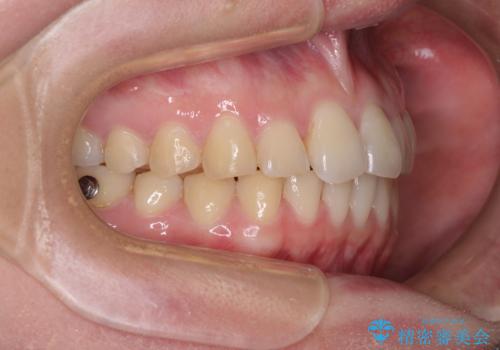

- 食いしばりが気になっていたとのことで来院された患者様です。

当初は睡眠時のマウスピースのみの製作をご希望でしたが、矯正治療の提案をしたところ、インビザラインにて矯正治療を行うこととなりました。

矯正治療中に食いしばりがより強くなることがあるため、半年に1回のペースでボツリヌストキシンによる咬合力緩和を並行して行うこととしました。

咬合力の緩和と食いしばりがちな咬み合わせが改善され、顎の負担が大幅に軽減されました。